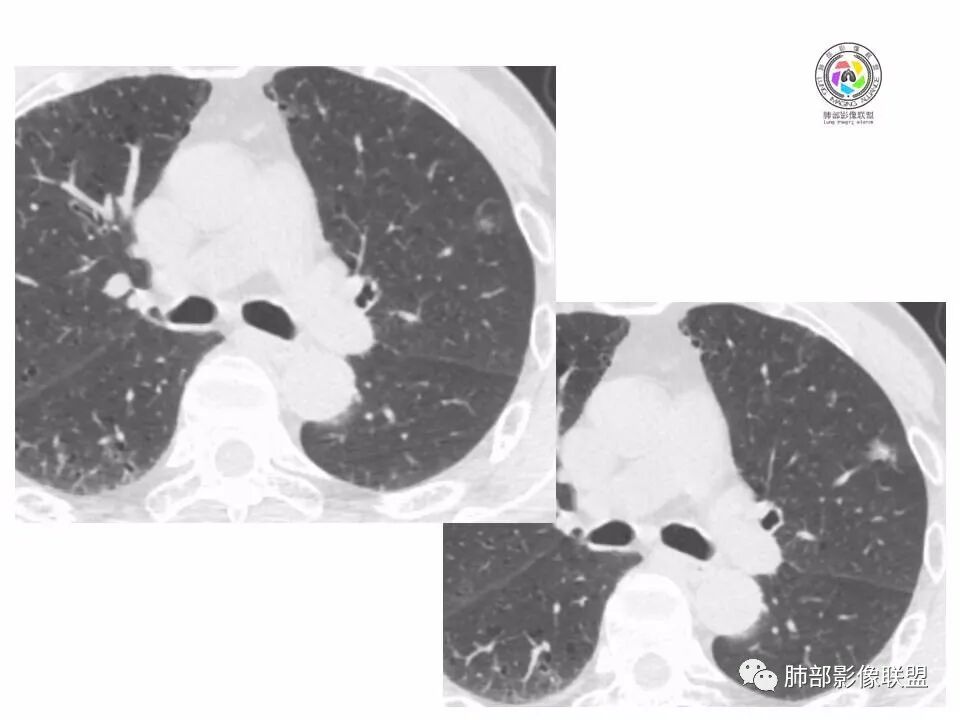

左肺上叶小结节,边缘毛糙,血管集束,支气管截断,强化较明显,但U型凹陷,部分边缘平直,总体感觉恶性大于良性,首选腺癌,鉴别炎性肉芽肿。

左上肺结节,月牙征,边缘纠集有收缩力,小空泡,血管增粗进入,纵隔淋巴结增大,考虑恶性,隐球菌待排。

老年男性,左上肺结节,边缘毛糙,临近血管进入增粗,内部隐约可见小空泡或远端扩张支气管,血管集束并伴月牙铲,有个横断界面看似像脐凹征,常规考虑腺癌,鉴别隐球。

结节,分叶,边缘毛糙,小空泡,血管集束并伴月牙铲,有强化,老年男性,考虑腺癌,建议复查除外结核。

左肺上叶混合密度结节,边缘见边缘清楚磨玻璃,分叶,U型凹陷,首先考虑腺癌。

左肺上叶结节影,边缘可见分叶,血管集束及月牙铲征,病灶内见小空泡影,考虑腺癌可能。

结节密度不均匀,混合磨玻璃结节,大部分实性部分,边缘清,月牙铲征,肿瘤微血管征,考虑肺癌。

老年男性,体检发现左肺上叶结节,周围浅分叶伴磨玻璃影,有血管相连,U型凹陷,纵隔见肿大淋巴结,考虑为恶性,腺癌可能。

左肺形态不规则结节,边缘收缩,毛刺,有月牙铲,纵隔窗比肺窗小,不密实,近段血管与病灶相连,强化不明显,老年男性,综合考虑,恶性,腺癌,鉴别炎性结节。建议穿刺。

老年男性,左肺上叶结节,边界清,不规则,有毛刺,血管集束,空泡,边缘有气肿带,考虑腺癌,鉴别肉芽肿。

左肺上叶小结节,边缘毛糙,血管集束,支气管截断,有月牙铲,首选腺癌,鉴别炎性肉芽肿。

左上肺实性小结节,短毛刺,月牙铲,似见小空泡,血管集束,有轻度强化,首先考虑腺癌。

老年男性,肺气肿背景,左肺上叶小结节,大部分边缘平直,部分边缘膨隆,局部可见月牙铲,边缘少许磨玻璃,边界清晰,血管进入,轻度强化,首先考虑腺癌,常规抗炎后复查,除外炎性结节。

左上肺结节,短毛刺,空泡,月牙铲,脐凹征,考虑腺癌。

左肺上叶混合密度结节,边界清,分叶,毛刺,血管进入,月牙铲,有强化,首先考虑腺癌,有平直边,收缩力不明显,常规先抗炎。

左上肺结节分叶,边缘毛糙,小空泡可能,血管集束,月牙,纵隔窗面积小于肺窗,有磨玻璃成份,有强化,老年男性,白细胞高,恶性的征象都有,但磨玻璃的形态和边界不好评估,实性为主,看形态和边缘局部较散缺乏饱满感,顶着压力反着来猜炎性可能大。复查不消失会考虑腺癌或黏液腺癌。

老年男性,肺气肿背景,左肺上叶实性结节,边界清,边缘平直为主,细长毛刺,较明显强化,考虑炎性病灶,隐球?

老年男性,左肺上叶结节,边缘可见长毛刺、较软,并可见分叶,周围可见清楚磨玻璃密度,内可见空泡征,增强后呈均匀强化,良恶性征象都有,感觉收缩力不强,化验白细胞偏高,建议抗炎治疗后复查除外腺癌。

老年男性,左肺上叶混合密度结节,空泡,分叶,血管集束,有强化,考虑腺癌;细长软毛刺,血管走行自然,边缘有平直收缩,白细胞高,肿标正常,考虑炎性结节。猜炎性结节,鉴别腺癌。

左肺上叶前段mGGN,边缘见毛刺及月牙铲,考虑腺癌,需要薄层图像确认所见征象。

左肺上叶结节,分叶,边缘毛糙,小空泡,月牙铲,有强化,考虑浸润性腺癌,鉴别炎性肉芽肿。

患者老年男性,体检发现。查癌胚抗原不高。血常规血象升高。胸部CT:肺气肿背景,左肺上叶近胸膜下实性结节,边缘光滑,边界清楚,可见毛刺、血管集束、月牙铲征象,增强不明显,内可见低密度区,综合考虑恶性病变,腺癌可能大,鉴别结核及炎性结节。

老年男性,左肺上叶结节,周围浅分叶伴磨玻璃影,有血管相连,月牙铲。纵隔见肿大淋巴结,但白细胞高。腺癌首先,需排除炎性假瘤。抗炎治疗后复查。

老年男性,体检发现左肺结节,分叶、脐凹、月牙铲及月牙铲附近有边缘清楚的磨玻璃影,上述征像均指向恶性肿瘤,有疑问的地方:毛刺软无力,无胸膜牵拉及白细胞计数升高。整体是腺癌,需要抗议后复查以排除炎性病变。

图片有限,左肺上叶结节病灶,有张力,有收缩及小泡征,边缘可见月牙征,周围长毛刺及血管集束征,增强目测有中度以上强化,首先考虑恶性病变,腺癌。

左肺上叶前段小结节,边缘稍毛糙,月牙铲,血管进入可疑脐凹征,小空泡?增强有强化,老年男性,要高度警惕腺癌,但感觉毛刺偏细软,周围磨玻璃不明显,常规查隐球菌荚膜抗原除外隐球菌,血象高,抗炎后短期复查除外炎性结节。

左肺上叶mGGN,边缘收缩平直为主,肺窗显示清楚,纵隔窗体积缩小,未见胸膜牵拉,倾向感染性结节,隔期复查。